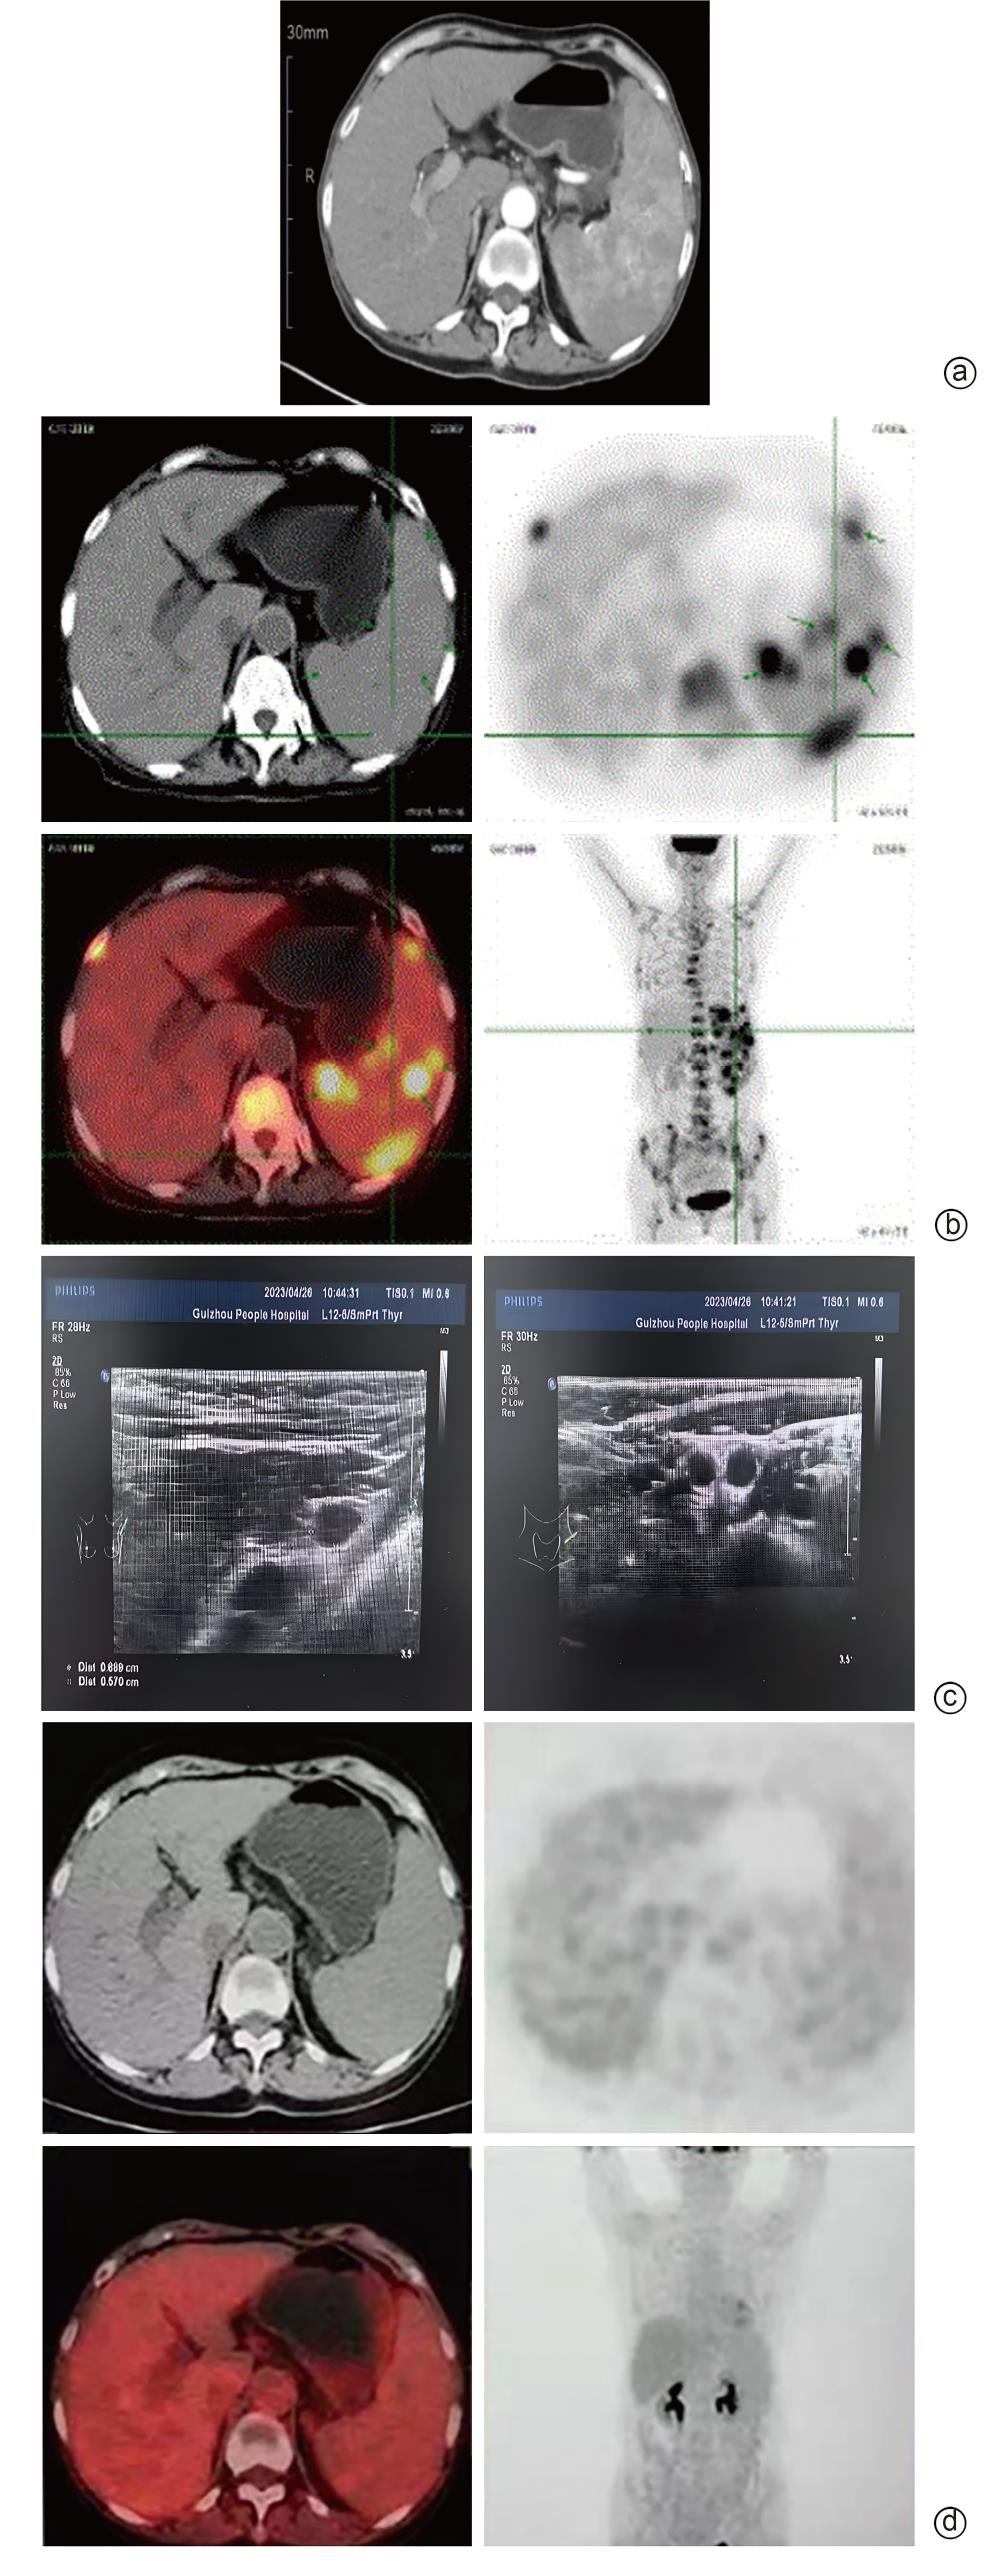

Primary splenic lymphoma misdiagnosed as Sjögren’s syndrome with liver cirrhosis: A case report

Chengcheng LI, Yuhong LIU, Lu WANG, Hong PENG, Xinhua LUO, Hong LI

2025, 41(9): 1883-1887. DOI: 10.12449/JCH250925

Abstract(459) HTML (106) PDF (5783KB)(64)

Abstract:

Primary splenic lymphoma is a rare malignant neoplasm, with similar clinical manifestations to Sjogren’s syndrome and liver cirrhosis, which often leads to misdiagnosis. This article reports a case of primary splenic lymphoma misdiagnosed as Sjogren’s syndrome with liver cirrhosis, in order to improve the understanding of primary splenic lymphoma, Sjogren’s syndrome, and liver cirrhosis and avoid misdiagnosis and treatment delay.